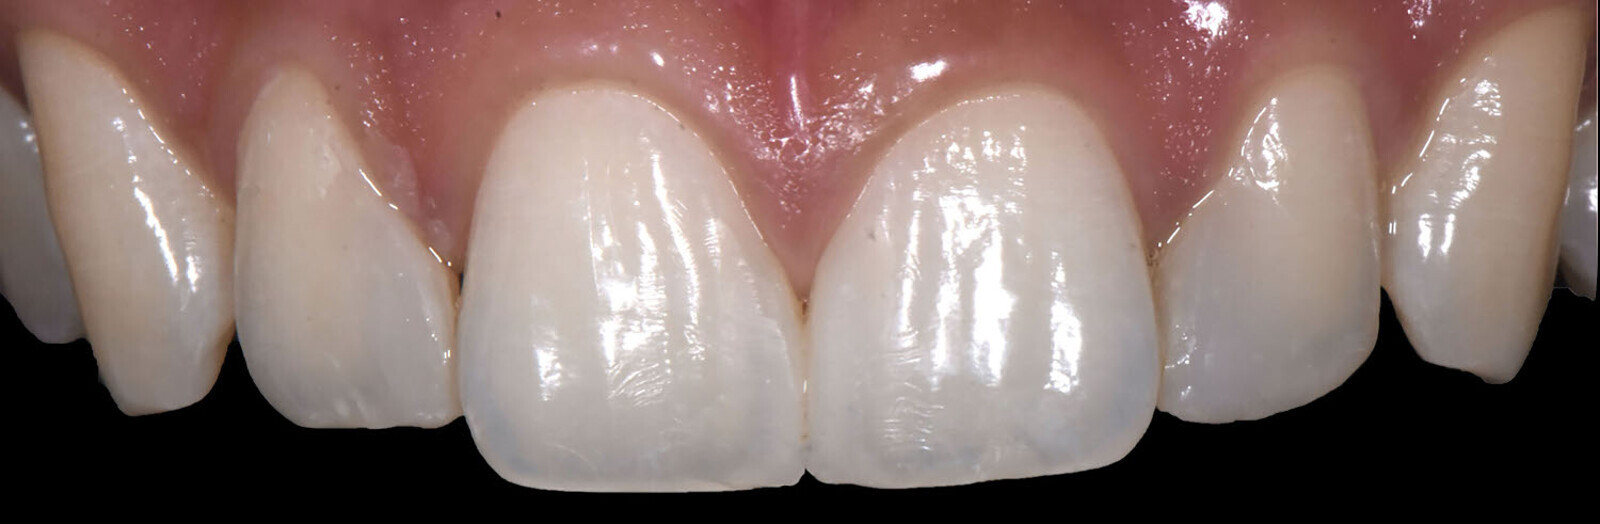

Fig. 12: Marked transition lines.

Texturing of the surface Transition lines were drawn on the vestibular surfaces of teeth #12–21 using a pencil (Fig. 12) to provide guidance for the contouring.12 Lastly, the texture steps were performed (Fig. 13), creating vertical texture with a rough appearance for the demarcation of vestibular features and giving an appropriate curvature to the area of the contact point;13 as well as creating micro-texture: after proper mirror polishing, restorations can be made brighter depending on how the incident light is dispersed, absorbed and reflected on the irregular vestibular surface geometry (Figs. 14 & 15).14

Fig. 13: Achievement of the surface texture.